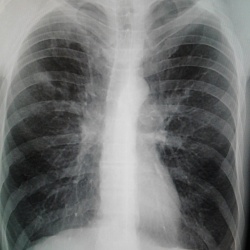

Мужчина 1975 г.р.,проходит флг,в направлении от терапевта-левосторонняя пневмония?планирую отправить в ПТД,но хотелось б послушать ваши мнения по данным снимкам.Спасибо.